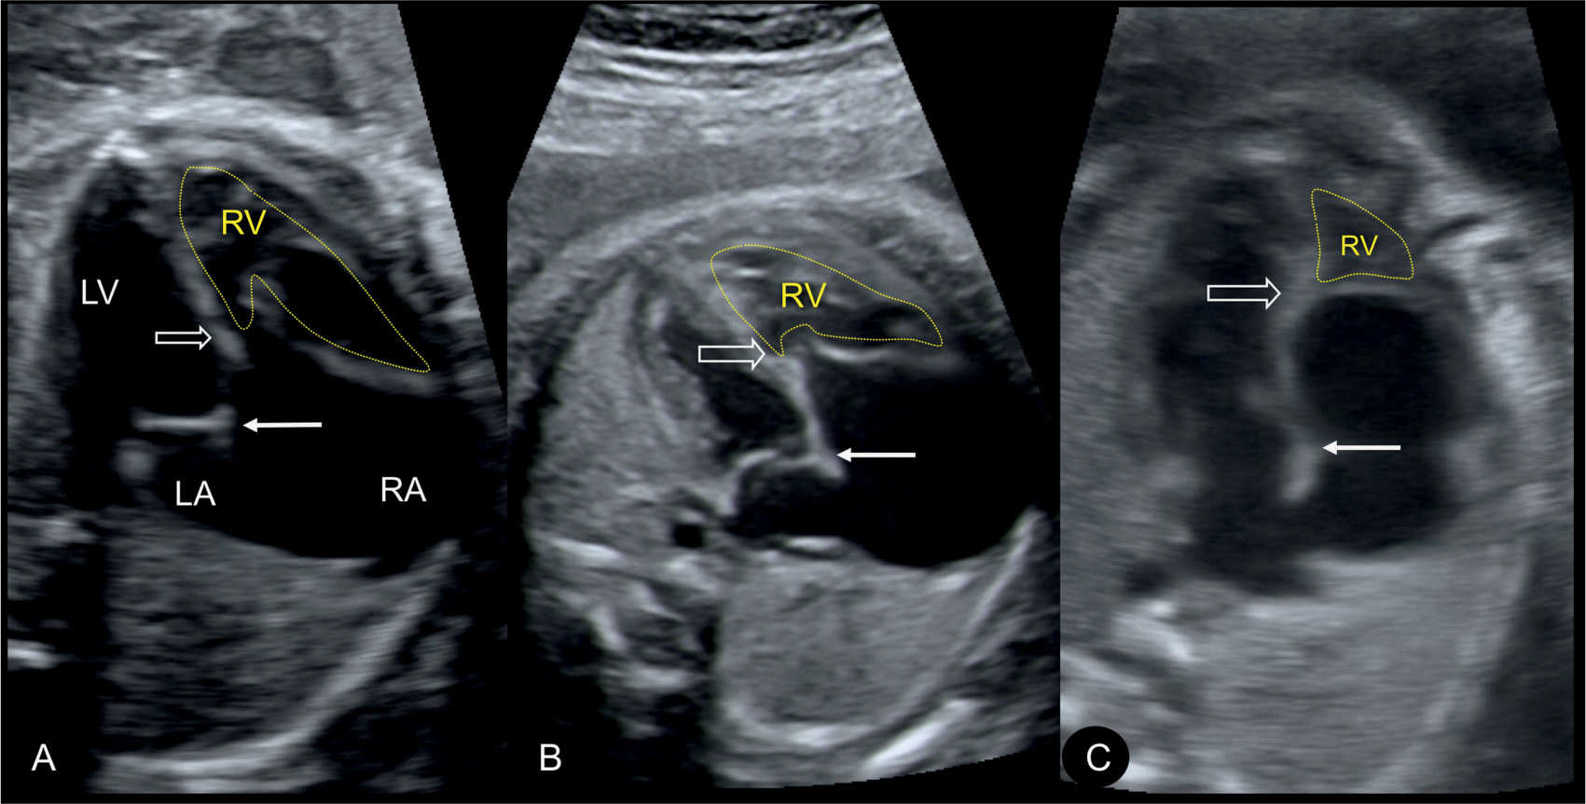

From obgynkey.com

Ebstein Anomaly, Tricuspid Valve Dysplasia, and Tricuspid Regurgitation Ebstein Anomaly It affects the tricuspid valve in your heart and can cause an enlarged heart, irregular heartbeat and heart failure. Ebstein anomaly is a rare congenital cardiac defect that consists of variable apical displacement from the annulus and dysplasia of the septal and. This means it's a congenital heart defect. The severity of the defect varies widely. The tricuspid valve is. Ebstein Anomaly.

Ebstein Anomaly, Tricuspid Valve Dysplasia, and Tricuspid Regurgitation Ebstein Anomaly Ebstein’s anomaly is a rare birth defect. This means it's a congenital heart defect. The severity of the defect varies widely. Ebstein anomaly is a rare congenital heart disease characterized by apical. It affects the tricuspid valve in your heart and can cause an enlarged heart, irregular heartbeat and heart failure. The tricuspid valve is incorrectly formed. Ebstein anomaly is. Ebstein Anomaly.

Ebstein Anomaly, Tricuspid Valve Dysplasia, and Tricuspid Regurgitation Ebstein Anomaly It affects the tricuspid valve in your heart and can cause an enlarged heart, irregular heartbeat and heart failure. The severity of the defect varies widely. This means it's a congenital heart defect. Ebstein’s anomaly is a rare birth defect. Ebstein anomaly is a rare congenital cardiac defect that consists of variable apical displacement from the annulus and dysplasia of. Ebstein Anomaly.

Ebstein Anomaly, Tricuspid Valve Dysplasia, and Tricuspid Regurgitation Ebstein Anomaly Ebstein anomaly is a rare congenital heart disease characterized by apical. Ebstein anomaly is a rare heart problem present at birth. The severity of the defect varies widely. Ebstein anomaly is an uncommon congenital cardiac anomaly, characterized by a variable developmental anomaly of the tricuspid. The tricuspid valve is incorrectly formed. This means it's a congenital heart defect. Ebstein anomaly. Ebstein Anomaly.